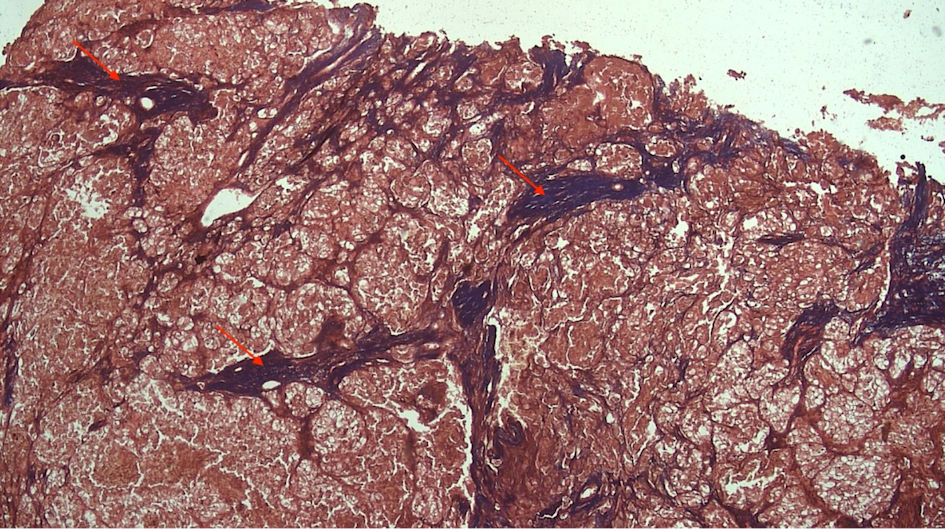

Subjects involved in this research were similar in age. However, most of the subjects involved in this study were male (Table 1). FAP expression correlated positively with TACS despite the tumor being in the stromal or intratumoral (y = 4.5x - 0.6667 in intratumoral tumors, and y = 4.5x - 1.6667 in stromal tumors, as seen in Figure 1). According to the Spearman rho test results, there was a positive correlation between the TACS degree to intratumor samples (96%) and stromal samples (84%), respectively accounted for 25 and 22 patients (y = 0.5x + 0.8; P = 0.0001) (Fig. 2). Histopathological images of TAC-3 collagen deposits (Fig. 3), and positive intratumoral and stromal FAP are illustrated below (Figs. 4, 5).

![]() Click for large image | Figure 3. TAC-3 collagen deposits located perpendicularly to the mass tumor (red arrow). TACS: tumor-associated collagen signature. |

As it is not described well, the collagen characteristics of RCC have a correlation to tumor behavior as well as the clinical factors of other malignancies [15]. In the invasive phase of malignancy, the collagen fibers are assumed to align perpendicularly to the tumor boundary. These changes, of course, have significant differences in the densities as well as in the fiber alignment between those in grade 1 and grade 4 RCC. This condition also demonstrates that the ability to reorganize collagen fibers within a random collagen matrix is shown by the tumor to facilitate the invasion. This ability to organize collagen as “a scaffold” suggested an important step in tumorigenesis. Although this active process has not yet been investigated, it is significant to determine the greatest collagen alignment within the most aggressive of RCCs. However, some studies suggested that the features of the current collagen could not be used as a diagnostic method due to a lack of applicable discriminant ability [15, 16].